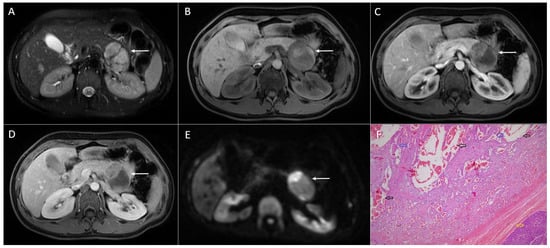

3.3. Intrapancreatic Accessory Spleen